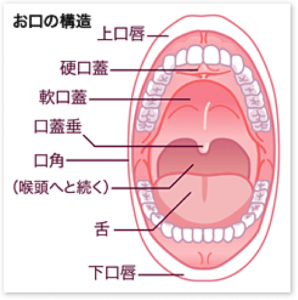

口の中の病気は、虫歯以外にもたくさんあります。普段あまり口の中を見る機会がない方は、虫歯で歯科を受診した際に指摘されることもあります。今回のコラムでは、そのなかで代表的なものを紹介していきます。

普段、鏡を見る機会はたくさんあると思います。しかし、口の中はあまり見たことがないと思います。毎日の歯磨きの時も鏡をみながらしても、口の中までは見ていないと思います。口の中の病気には、すぐに痛みの出るものと、そうでないものがあります。虫歯などは、比較的早期に痛みが出ますので分かり易いのですが、口腔粘膜の病気は痛みがわかりにくく、発見が遅れることがありますので、普段から口の中を見るようすることが大切です。また、歯科の定期健診を受けることにより虫歯だけでなく、粘膜の病気も早期に発見することができます。